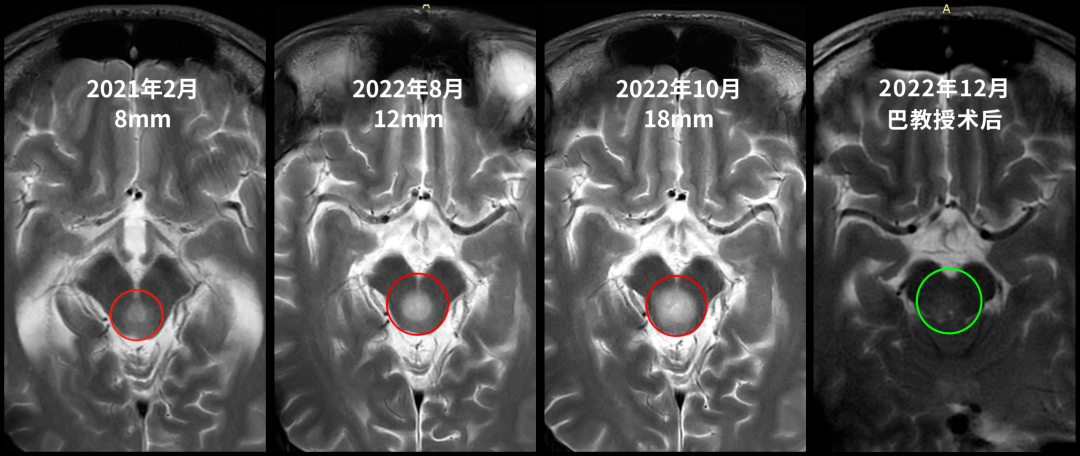

中脑顶盖胶质瘤有一个让人误判的特质:它确实可以在相当长的...